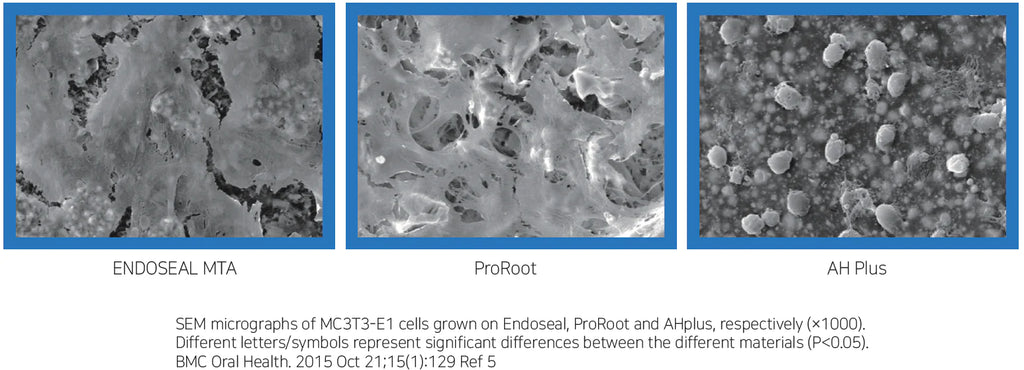

ENDOSEAL MTA is a paste-type root canal sealer based on pozzolan cement that has excellent physical and biological properties of MTA. It is premixed and pre-loaded in a syringe that allows direct application of the sealer into the root canal without requiring powder/liquid mixing, unlike other products. The product has outstanding flowability and maneuverability, which makes it possible to completely fill the root canal system including accessory and lateral canals. It is eugenol-free and will not impede adhesion inside the root canal.